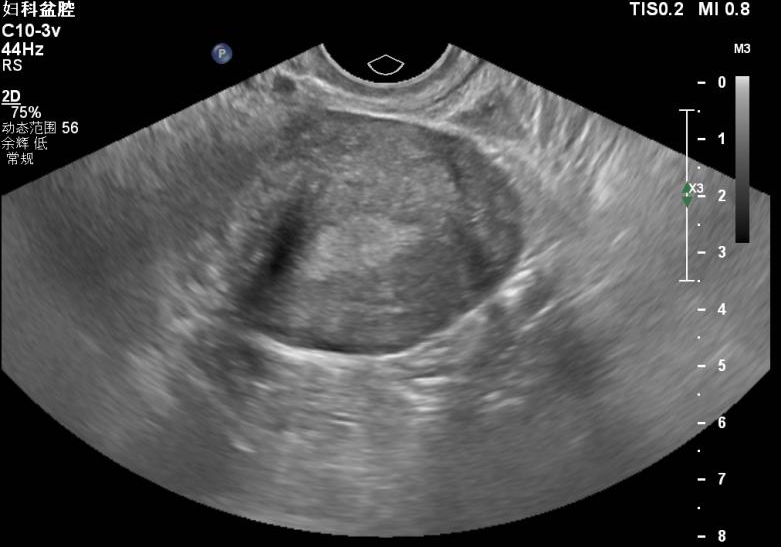

患者张xx,女,29岁。就诊时间:2021年3月20日。 主诉:继发性痛经伴进行性加重2+年。 现病史:患者自2018年10月份开始无明显诱因出现月经期下腹痛,起初未在意,未就诊。现因痛经进行性加重,NRS疼痛评分5分,伴性交痛,为进一步诊治就诊。 既往史:既往体健,无特殊既往史可询。 个人史:无特殊个人史可询。 月经史:14岁初潮,5/28天,经量中等,2018年开始出现痛经。 婚育史:22岁结婚,孕2产1,2015年足月顺产分娩1女,2017年自然流产1次。 家族史:无特殊家族史可询。 妇科检查:外阴已产式,阴道畅,宫颈光滑,大小正常,质中,子宫后位,宫体大小正常,形态规则,活动欠佳,后穹隆可及触痛结节,右侧附件区可扪及一个大小约7cm*6cm*5cm的囊性肿物,活动欠佳,伴触痛,左侧附件区未扪及明显异常。 辅助检查: B超:子宫后位,宫体大小正常,宫腔线居中,内膜厚4mm,肌层无明显增厚,右侧附件区可见大小约76mm*58mm*54mm的囊性肿物,内可见密集细弱光点,左侧附件区未见显异常回声。 术前B超:右侧卵巢囊肿 诊断: 诊断依据: 处理:患者继发性痛经伴进行性加重,B超检查提示卵巢子宫内膜异位囊肿>4cm,患者近期内有生育要求,予以行腹腔镜下卵巢子宫内膜异位囊肿剥除术+盆腔子宫内膜异位病灶切除术,术后予以地屈孕酮口服减少内异症复发并随访。 1.诊疗思路: (1)长期管理,坚持以临床问题为导向,以患者为中心,分年龄阶段处理,综合治疗; (2)基于临床诊断尽早开始经验性药物治疗; (3)规范手术时机,注意保护卵巢功能和生育力,使患者的手术获益最大化; (4)保守性手术后进行药物长期管理,综合治疗,预防复发; (5)内异症患者应定期复查,对有恶变高危因素的患者应警惕恶变。 患者继发性痛经伴进行性加重,B超检查提示卵巢子宫内膜异位囊肿>4cm,根据中国子宫内膜异位症诊治指南(第三版),有手术指征,针对该患者的病情,我们采取了腹腔镜手术+术后药物长期管理的治疗策略,并鼓励患者恢复后尽早备孕。 2.手术治疗: 术后病理: (1)右侧卵巢子宫内膜异位囊肿; (2)(盆腔病灶)可见含铁血黄素陈旧,考虑为子宫内膜异位; (3)患者术后恢复良好,于2021年3月26日出院。 3.术后长期管理: 4.术后随访: 妇科检查:阴道后穹隆触痛结节不明显,双侧附件区未扪及明显异常。复查盆腔彩超未提示巧囊复发。嘱患者继续规律服药。 第一次复查 ②2021-12-06,患者第二次随访。痛经情况较术前明显缓解,NRS疼痛评分1分。患者期间一直遵医嘱规律服用地屈孕酮,月经正常。 妇科检查:阴道后穹隆未扪及触痛结节,双侧附件区未扪及明显异常。复查盆腔彩超未提示巧囊复发。嘱患者继续规律服药。 第二次复查 ③2022-04-17,患者第三次随访。患者自术后已规律服用地屈孕酮1年,月经正常,痛经已完全缓解,无性交痛,NRS疼痛评分0分。 妇科检查:阴道后穹隆未扪及触痛结节,双侧附件区未扪及明显异常。复查盆腔彩超未提示巧囊复发。建议患者可继续规律服用地屈孕酮。 第三次复查 子宫内膜异位症是生育期女性的常见病,多发病,约10%的生育期女性患有内异症。其主要症状是下腹痛和痛经,还可表现为慢性盆腔痛和性交痛,除此之外还有不孕、月经异常等表现。内异症可影响生殖系统各个部分,导致卵巢功能受损,生育力下降。2021年中国子宫内膜异位症诊治指南(第三版)指出内异症治疗应以患者为中心,分年龄阶段处理,规范手术时机,在保守性手术后应予以长期药物管理及定期复查[1]。 内异症的药物治疗主要分为非甾体类抗炎药(NSAID)、孕激素类、复方口服避孕药(COC)、促性腺激素释放激素激动剂(GnRH-a)及中药等。其中孕激素又包括地屈孕酮和高效孕激素,如地诺孕素、甲羟孕酮、左炔诺孕酮宫内释放系统(LNG-IUS)[2-3]。 地屈孕酮的优势在于控制内异症的同时不抑制排卵,适合有生育需求的患者[4]。全周期口服地屈孕酮片10-20mg/d,可有效控制内异症,同时可改善孕激素抵抗,增加妊娠机会[5]。 本病例中患者有明确的近期内生育要求,故不适宜予以GnRH-a、COC、地诺孕素等药物;同时患者EFI评分7分,患者拒绝试管婴儿等辅助生殖技术。因此,我们在与患者及家属沟通后给予患者月经第5-25天,地屈孕酮10mg/d,口服来减少内异症的复发并在服药前给患者做了乳腺彩超排除了乳腺结节。患者服药3个月即感到痛经明显缓解,术后规律服药1年后痛经完全消失,起到了良好的治疗效果。地屈孕酮得益于其服药期间不干扰受精卵着床,增强自然受孕能力,对有生育需求的患者具有优势[6]。同时,长期服用地屈孕酮对肝脏影响小,不引起骨质疏松,是内异症长期管理的优选药物之一[7-8]。 参考文献: 赵晨阳 医生 湖南省郴州市第一人民医院(湘南学院第一附属医院) 湖南省郴州市第一人民医院(湘南学院第一附属医院)妇科 副主任医师,医学硕士,毕业于中南大学湘雅医学院 ❖湖南省郴州市妇产科专业委员会秘书 ❖主攻方向:妇科恶性肿瘤规范化治疗和妇科微创手术 ❖目前主持湘南学院校级课题1项,院级课题1项,院内新技术项目1项

3.B超检查提示右侧附件区可见大小约76mm*58mm*54mm的囊性肿物,内可见密集细弱光点。